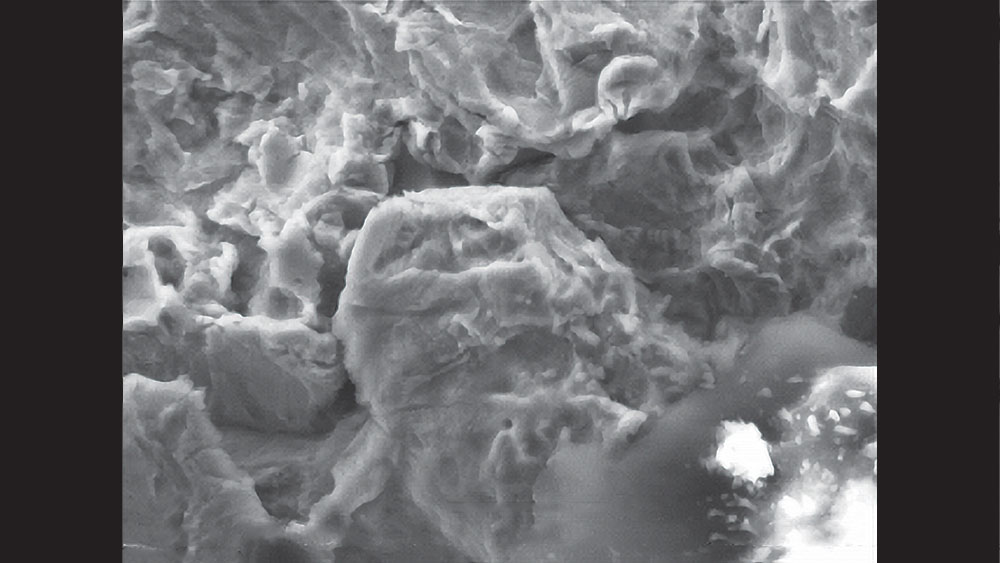

cm1401-rd-corner-efficacy-hahn-tapered-system-04a

cm1401-rd-corner-efficacy-hahn-tapered-system-04b

Figures 4a, 4b: Hahn Tapered Implants have multiple features that contribute to bone preservation and health, including coronal microthreads (4a) and a resorbable blast media surface (4b).

• The implant is treated with resorbable blast media (RBM), which involves a blasting process that texturizes the titanium surface of the implant and results in an ultra-clean, rough surface that has been proven ideal for bone integration and health.5